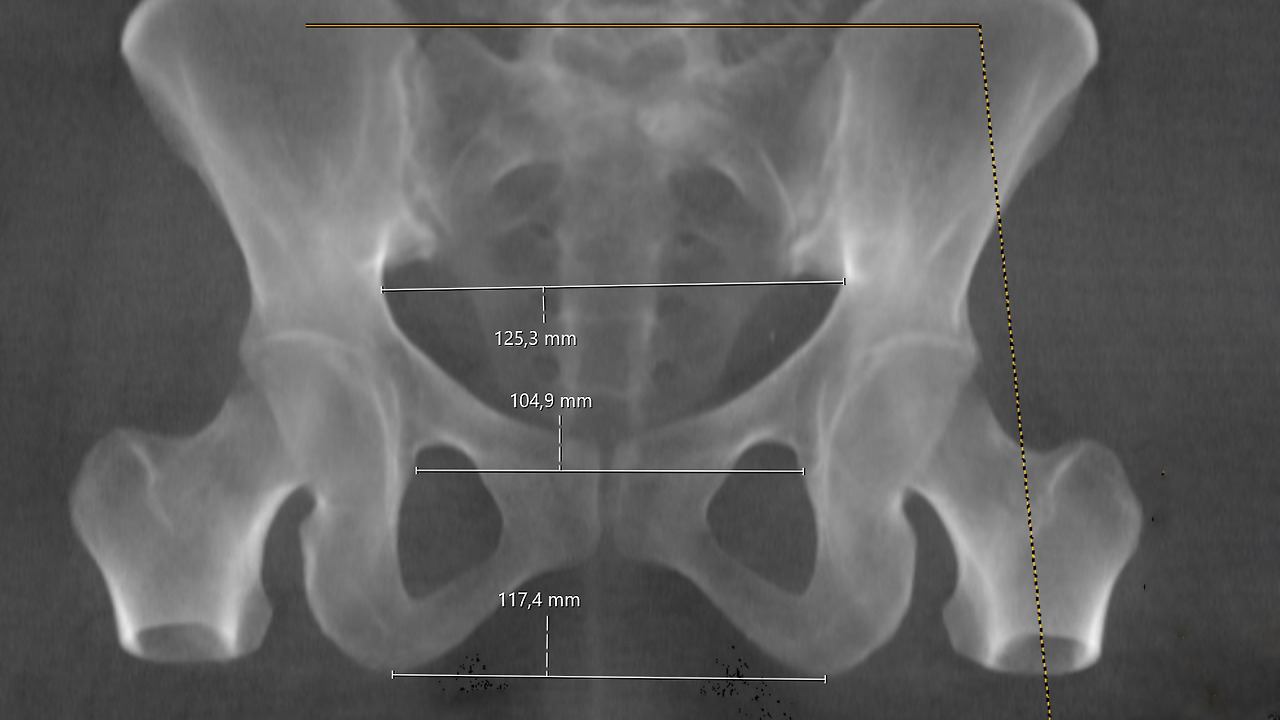

--협골반 (아두 골반 불균형)의 예측--

이중 진통 2기에 난산을 잘 초래하는 협골반에 대하여 말씀드리겠습니다.

협골반인지 아닌지 진단하는 것은 쉬운 일이 아닙니다.

골반의 넓이를 측정하기 위해 18세기에는 골반의 크기를 측정하는 골반 계측기 (Pelvimeter)가 사용되었습니다.

골반 계측기는 보시는 그림처럼 산도 안으로 집게발처럼 생긴 기구를 넣어서 벌린 후 그 길이를 측정해 보는 기구입니다. 골반 측정기는 사용하기 불편하고 부정확한 점 때문에 20세기 초 X선이 발견되면서 골반 측정 X 선 검사 (Pelvimetry)로 대체되었습니다.

골반 X선 검사는 골반의 가장 좁은 뼈 부분 (ischial spine)의 거리를 정확하게 측정할 수 있기는 하지만 검사 시 사용한 X 선으로 인해 태아의 골수에 영향을 줍니다. 그런 검사를 받고 태어난 아기들은 나중에 백혈병 등의 악성 질환이 발생할 위험이 높아진다는 사실이 밝혀져서 지금은 사용하지 않습니다.

대신 지금은 내진이라고 하여 손으로 만져 보는 진찰법을 사용합니다. 손가락 두 개를 질안으로 넣어서 골반의 넓고 좁은 정도를 판단하는 방법입니다. 그러나 내진에 의한 골반 너비 측정은 개인차가 심한 주관적 판단에 의존하는 방법이라서 정확한 방법이라고 할 수는 없습니다. 의사마다 판단이 다를 수 있으며 그저 참고 자료 정도로 생각해야 합니다.